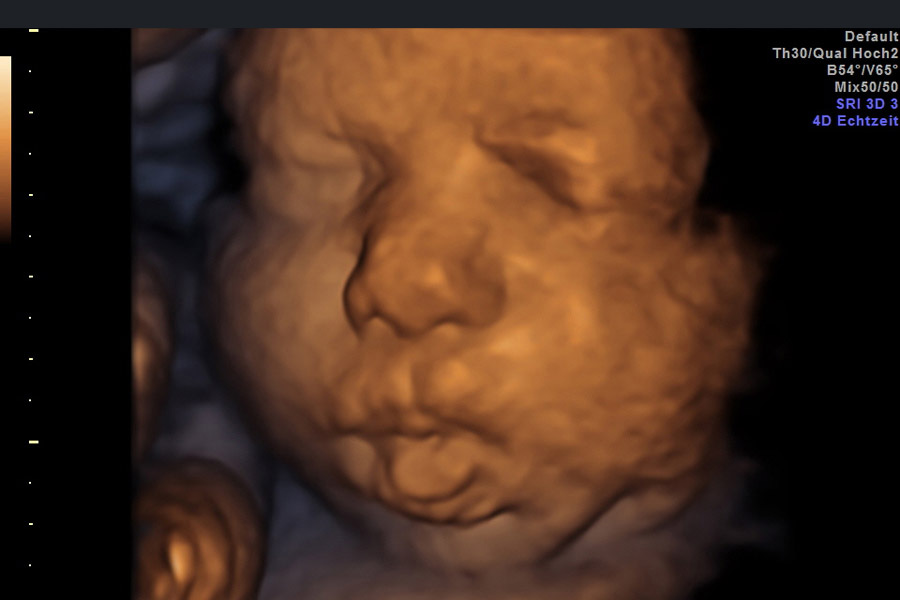

Pränatal-Medizin als Spezialisierung der Frauenheilkunde bedient sich hochauflösender Ultraschallgeräte zur Diagnostik fetaler Entwicklungsstörungen während der Schwangerschaft. Eines der modernsten Ultraschallsysteme, das Bilder in einer bisher nicht dagewesenen Qualität liefert, ist das Voluson E8, das im praenatarium von Dr. Kersten genutzt wird.

Eine 4D Transvaginalsonde hilft bei der Visualisierung und Erkennung von fetalen Fehlbildungen zu einem sehr frühen Zeitpunkt. Es verbessert die Diagnosesicherheit bei komplexen gynäkologischen Untersuchungen.